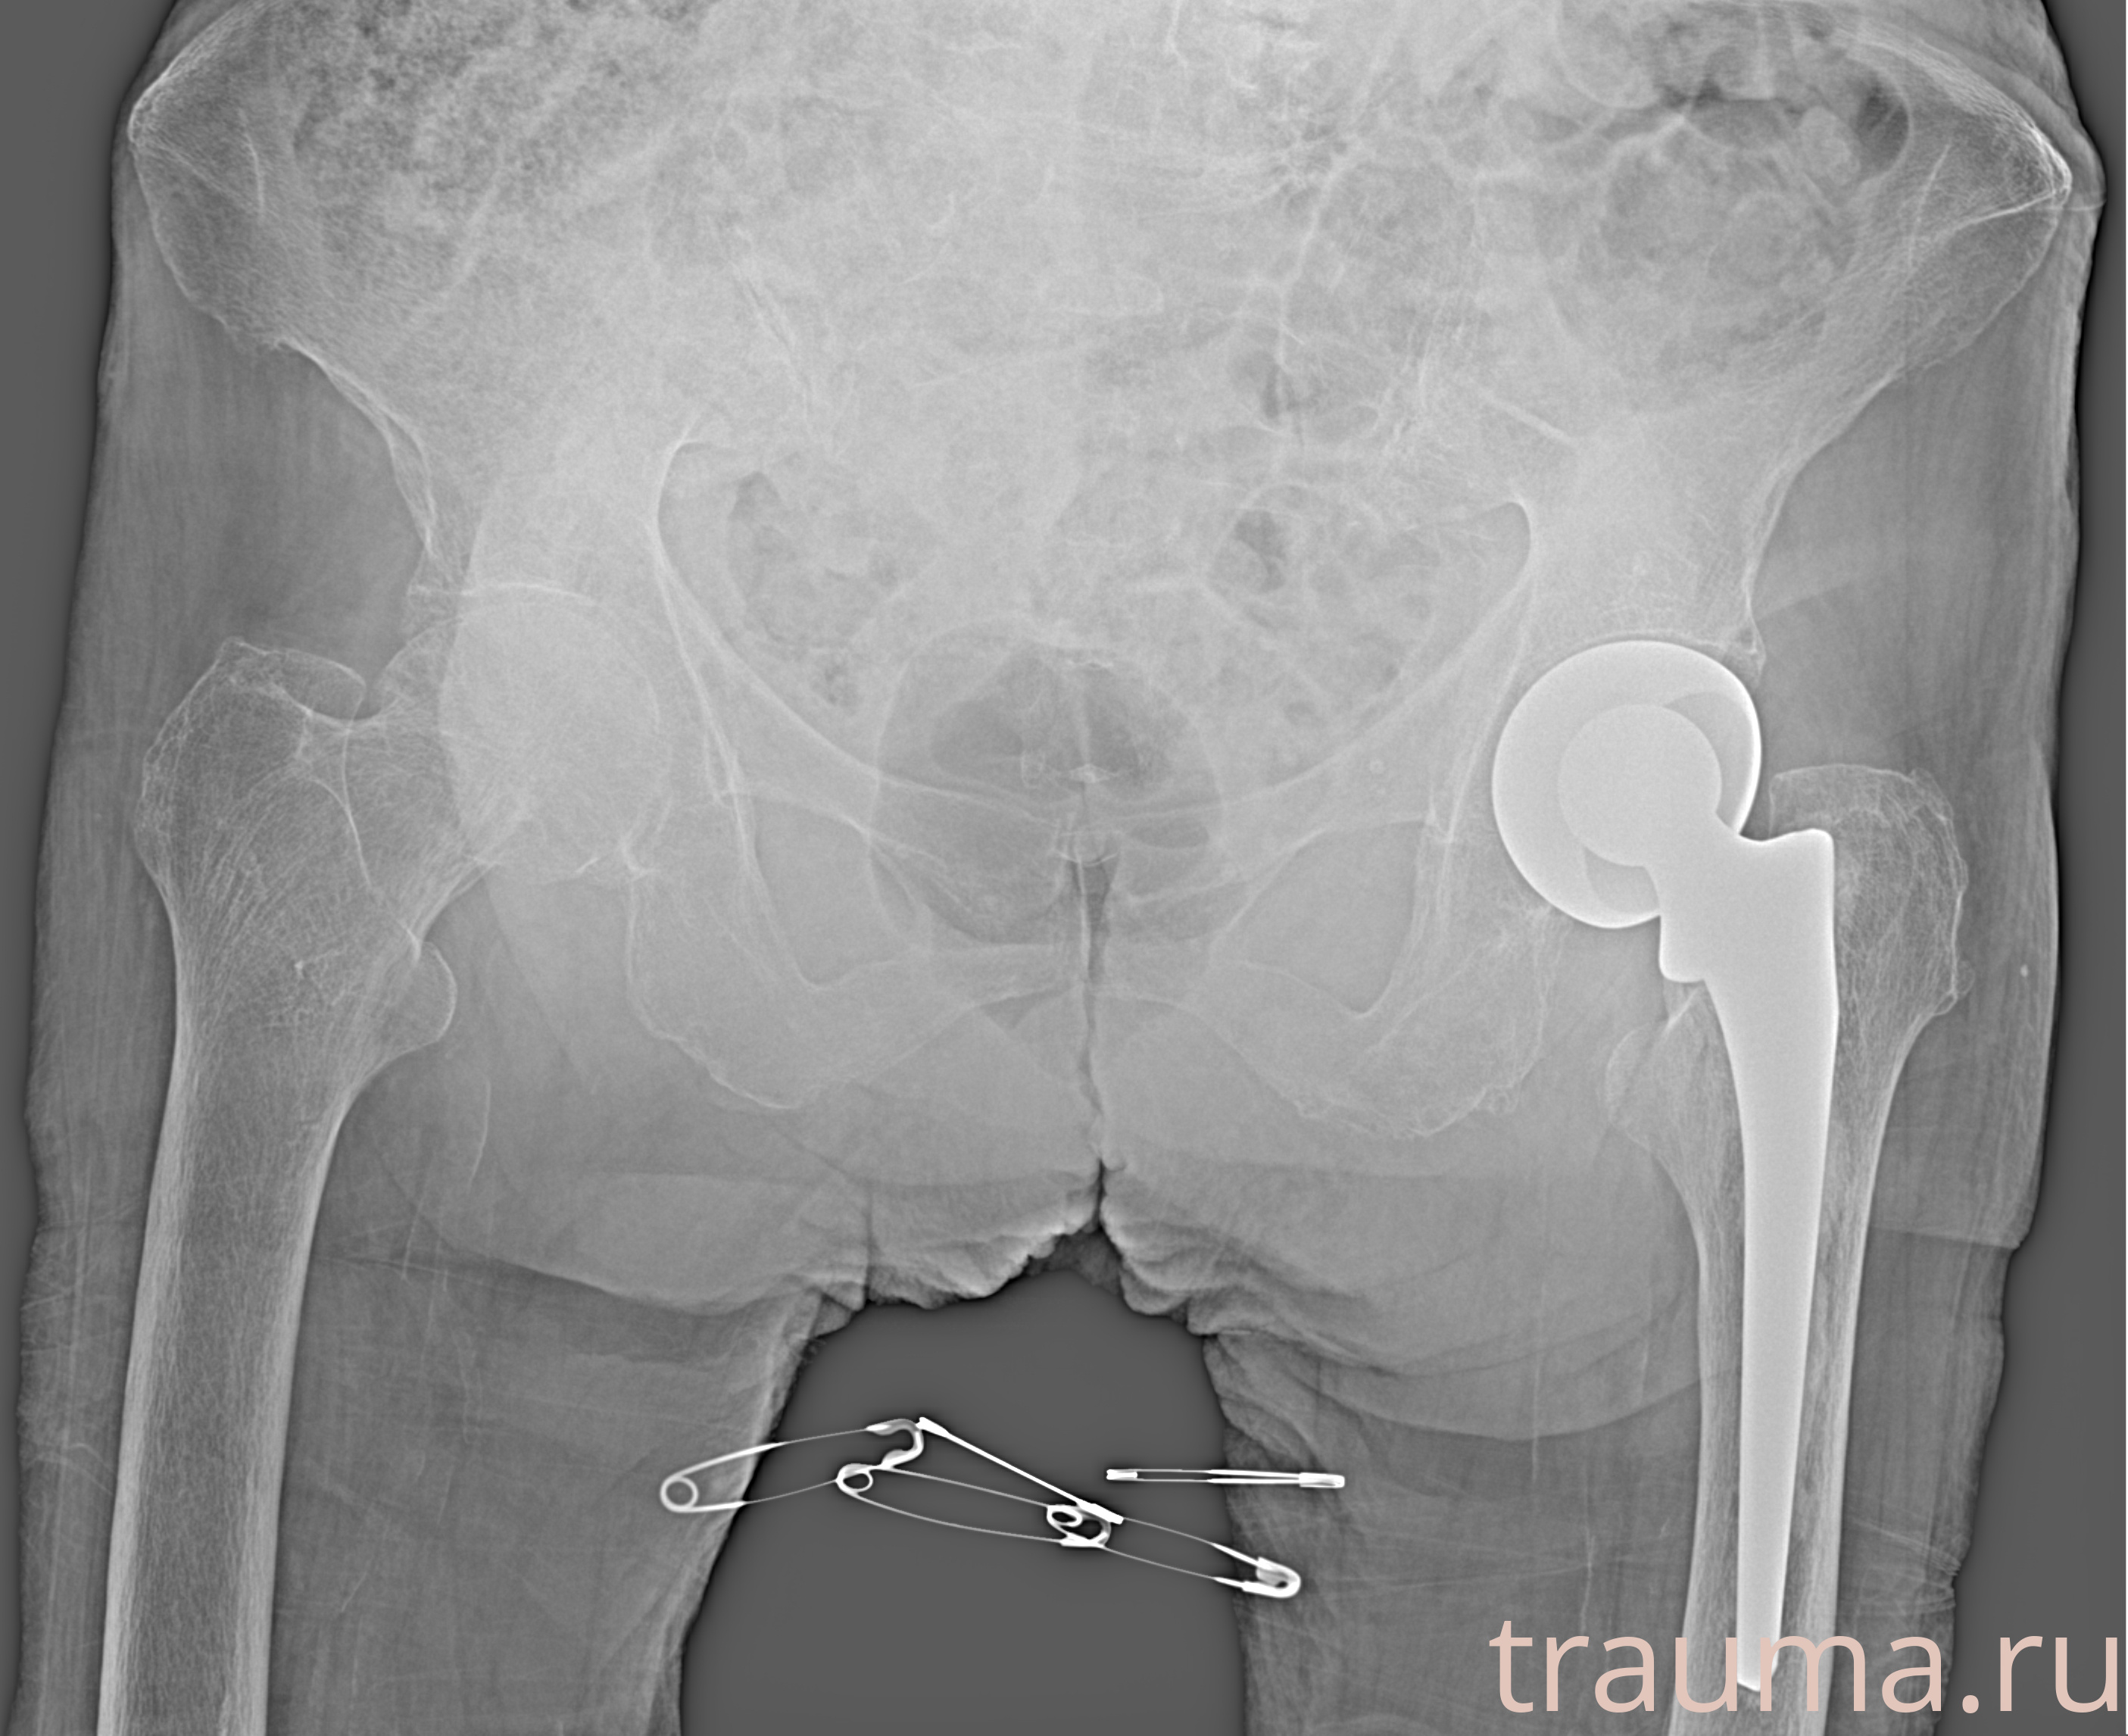

Рентгенограммы

Рентген на дому: по вашему адресу приезжает врач-рентгенолог, травматолог-ортопед с мобильным рентгеновским аппаратом, проводит диагностику травмы или заболевания, делает необходимые рентгенограммы, дает рекомендации по дальнейшему лечению. Получить качественные снимки в домашних условиях возможно благодаря уникальной методике, разработанной МосРентген Центром для института  Склифосовского